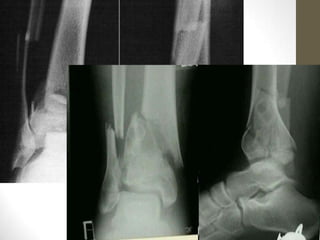

Mortise view:

Weber C

fracture with

open mortise

and widened

medial clear

space

= deltoid &

syndesmotic

ligament

tears, with

fracture

= surgical

referral